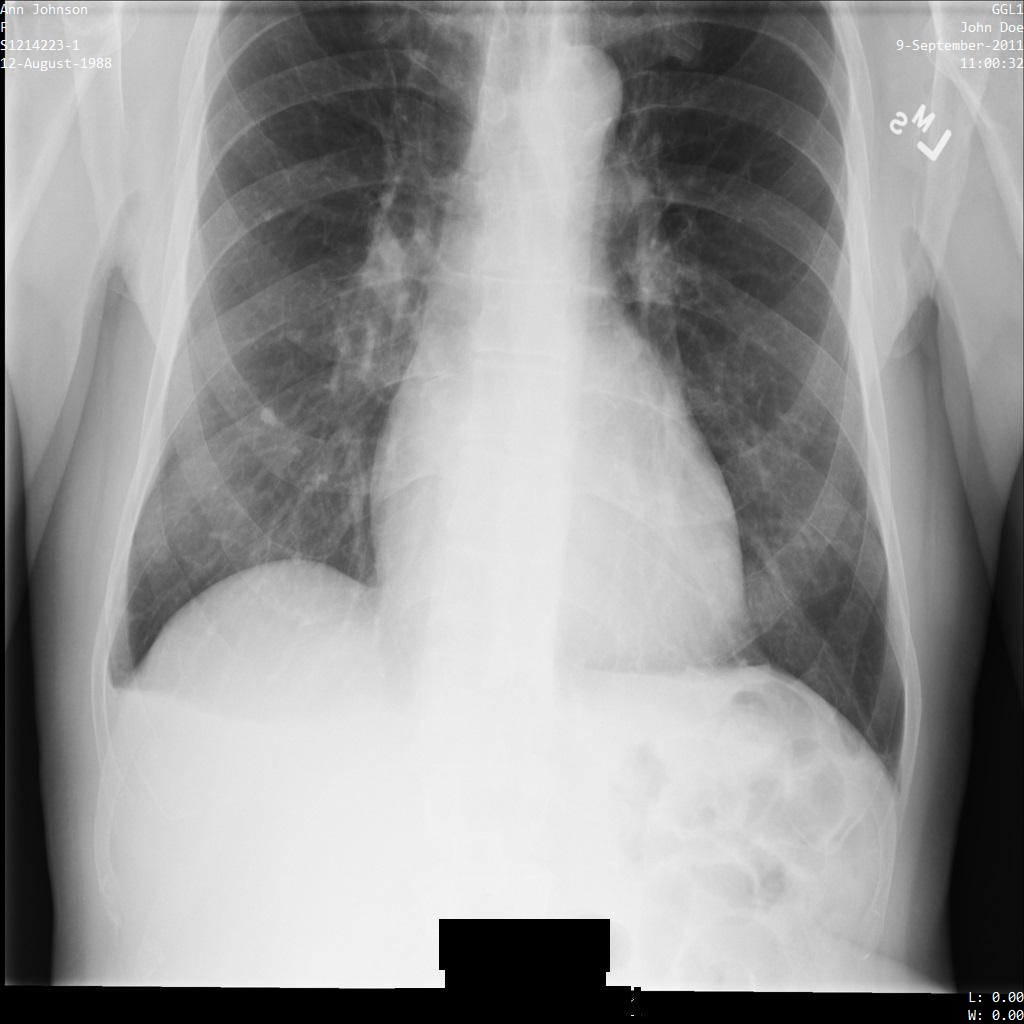

En cada una de las siguientes secciones, se proporcionan ejemplos de cómo desidentificar datos de DICOM mediante varios métodos. Se proporciona un resultado de la imagen desidentificada en cada muestra. En cada muestra, se usa la siguiente imagen original como su entrada:

Puedes comparar la imagen de salida de cada operación de desidentificación con esta imagen original para ver los efectos de la operación.

Después de enviar la imagen a la API de Cloud Healthcare, la imagen aparece de la siguiente manera. Mientras se ocultan los metadatos que se muestran en las esquinas superiores de la imagen, la información de salud protegida (PHI) quemado en la parte inferior de la imagen permanece. Para quitar también el texto quemado, consulta Oculta el texto quemado de las imágenes.